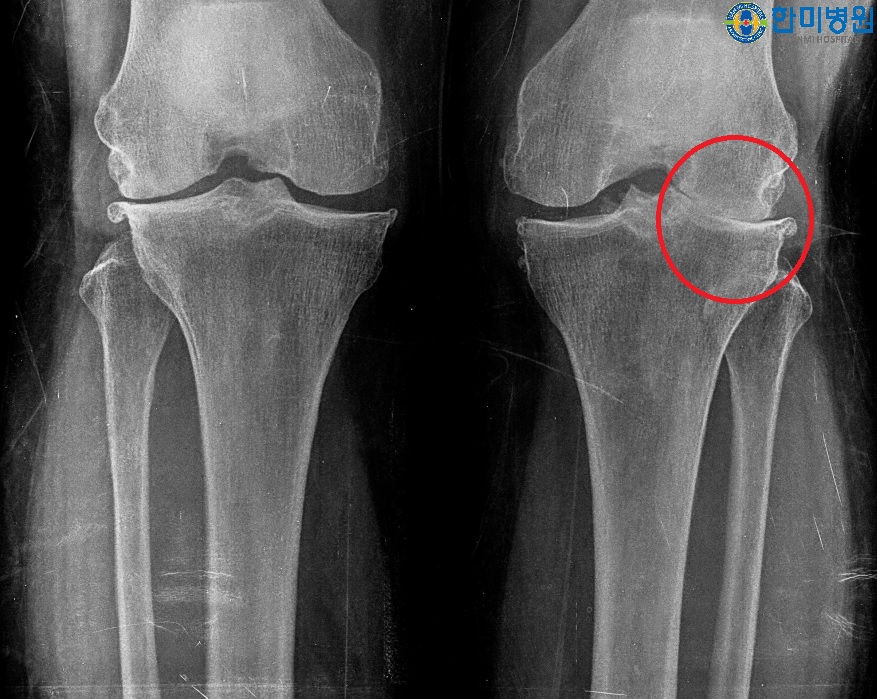

[무릎인공관절 수술 전 사진]

환자명 : 권**님

나 이 : 82세

수 술 일 : 2017년 06월 왼쪽 무릎인공관절 수술

수술 병원 : 대구 정형외과 한미병원

방 문 일 : 2018년 05월

환우분 상태 및 안내 : 수술 후 여행을 다닐만큼 좋은상태이며 오래 걸어다녀도 문제 없다고 하심수술 부위 굴곡 140° 정도 수월하시고 양반다리도 가능하심

수술받지 않은 우측다리는 통증이 조금 있다고 하심

평소 걷기 운동을 부지런히 하시고 근력운동의 중요성을 잘 아시고 본인 스스로 열심히 운동을 하심